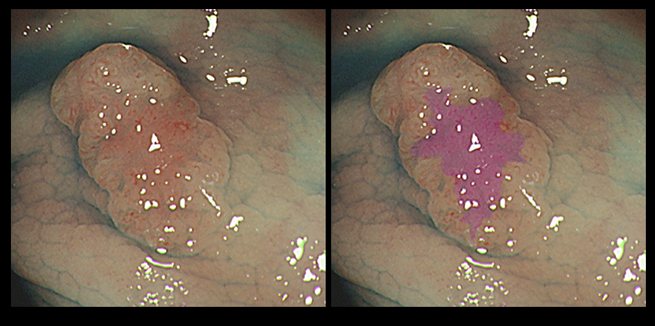

下のポリープは「小さいのに3つのサブクローン」があります。これは、短期間に遺伝子変異が3回起きた(=ゲノムが不安定)ことを意味します。すると、短期間のうちに、更に2つの遺伝子異常が蓄積される(=転移を起こす!)ことが予想されます。

このストーリーは最もシンプルな場合です。実際は、もっと複雑で、エピゲノム異常があったり、長い休眠期間(細胞老化 詳しく)があります。また3つのクローンが全て癌に進化し「サブクローンの混在した癌」になることもあります(Big Banモデル)。

「凸凹(不整)、陥凹しているポリープが危険」であることを、かなり昔から医師は経験的に知っていましたが、その機序(=腫瘍進化)の分子生物学的な解明は、始まったばかりです(⇒2018年文献 2021年文献)。